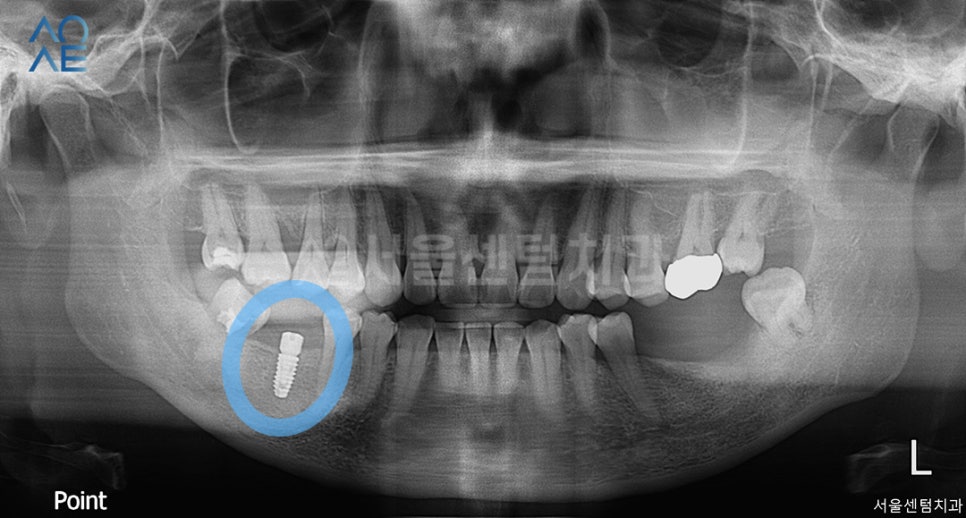

저희 치과에 처음 내원하셨을 때 찍은 x-ray로

이미 치아상실 상태인 것이 확인 가능하죠?

다행히 교합에 문제가 있거나

치아가 많이 쓰러지진 않았었는데요~

이 분의 경우에는

총 3개의 치아가 없었기 때문에

빨리 임플란트치료를 하시길 권유드렸습니다.